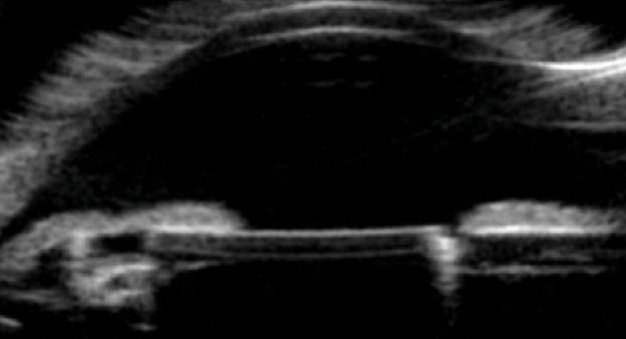

On examination, BCVA measured 20/30-2 in the affected eye. In the fellow eye, BCVA was 20/60, and there was amblyopia and an exotropia. The IOP measured 24 mm Hg OS on timolol, and the trabecular meshwork showed asymmetrically heavy pigmentation, with iris transillumination defects overlying the inferior optic edge (Figure 1). The IOL itself was mildly subluxated inferiorly, and ultrasound biomicroscopy (UBM) confirmed contact between the inferior iris and optic, with a Soemmering ring causing anterior displacement of the IOL (Figure 2). Visual field testing of the left eye demonstrated an early nasal step, and the optic nerve exhibited mild superior thinning.

Figure 2. In a vertical orientation (inferior angle is on the left), UBM demonstrated an inferiorly subluxated IOL, Soemmering ring, and optic-iris contact inferiorly.